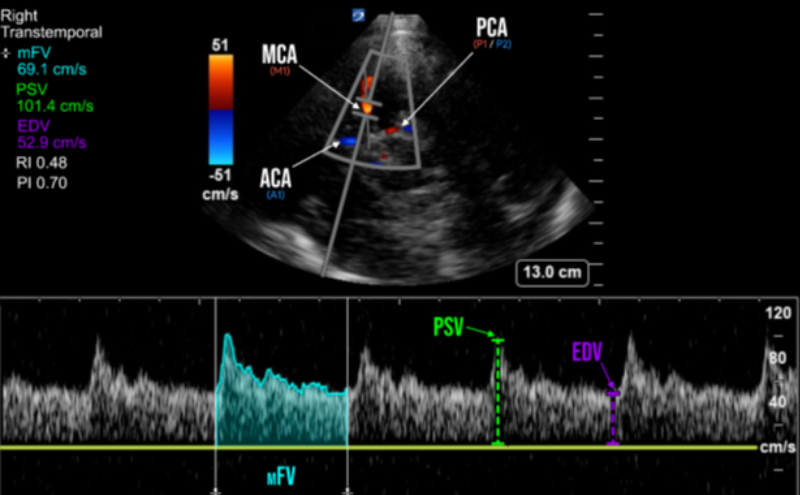

The transducer indicator should point towards the ipsilateral eye in the TCD pre-set, or towards the occiput if in Cardiac pre-set (Figure 1). The transducer is then oriented slightly upwards and anteriorly. Key landmarks of the transtemporal window include the hypoechoic, butterfly-shaped, cerebral peduncles, and are surrounded by the echogenic, star-shaped, basal cisterns. Color Doppler is then applied over this area and should reveal the circle of Willis. Multiple segments of the intracerebral vessels are able to be visualized in the transtemporal window, including those of the middle cerebral arteries (MCA), anterior cerebral arteries (ACA), and posterior cerebral arteries (PCA) (Figure 1 & 2). Pulsed-Wave Doppler is then applied with the gate placed through the ipsilateral MCA, which appears as a red color doppler signal traveling towards the probe. The normal spectral waveform of the MCA includes the following characteristics: a sharp systolic upstroke and a stepwise diastolic deceleration with positive end-diastolic flow. (Figure 2)

The primary parameter of TCD is known as the Mean Flow Velocity (mFV) (which is also called Time Average Mean, or TAM). MCA Vasospasm is defined by a mFV >120 cm/s, with severity further categorized as mild (>120 cm/s), moderate (>150 cm/s), and severe (>200 cm/s).1,3 mFV is calculated through measurement of the Peak-Systolic Velocity (PSV) and End-Diastolic Velocity (EDV) on spectral doppler, however some ultrasound machines are capable of automatic calculation of the mFV by tracing of the spectral doppler waveform (Figure 2).

Figure 2. Spectral doppler of the middle cerebral artery (MCA) and its measured parameters In addition to vasospasm, other pathologies causing cerebral hyperemia from global hyperdynamic blood flow (sepsis, fever, anemia, hypercapnia, etc.) can also increase MCA mFV. Further differentiation can be accomplished through calculation of the Lindegaard ratio, which is simply a ratio of the MCA mFV divided by the ipsilateral extracranial internal carotid artery (ICA) mFV. The Lindegaard ratio can thus not only help with differentiation between hyperemia and vasospasm, but is also another method of quantifying vasospasm severity.